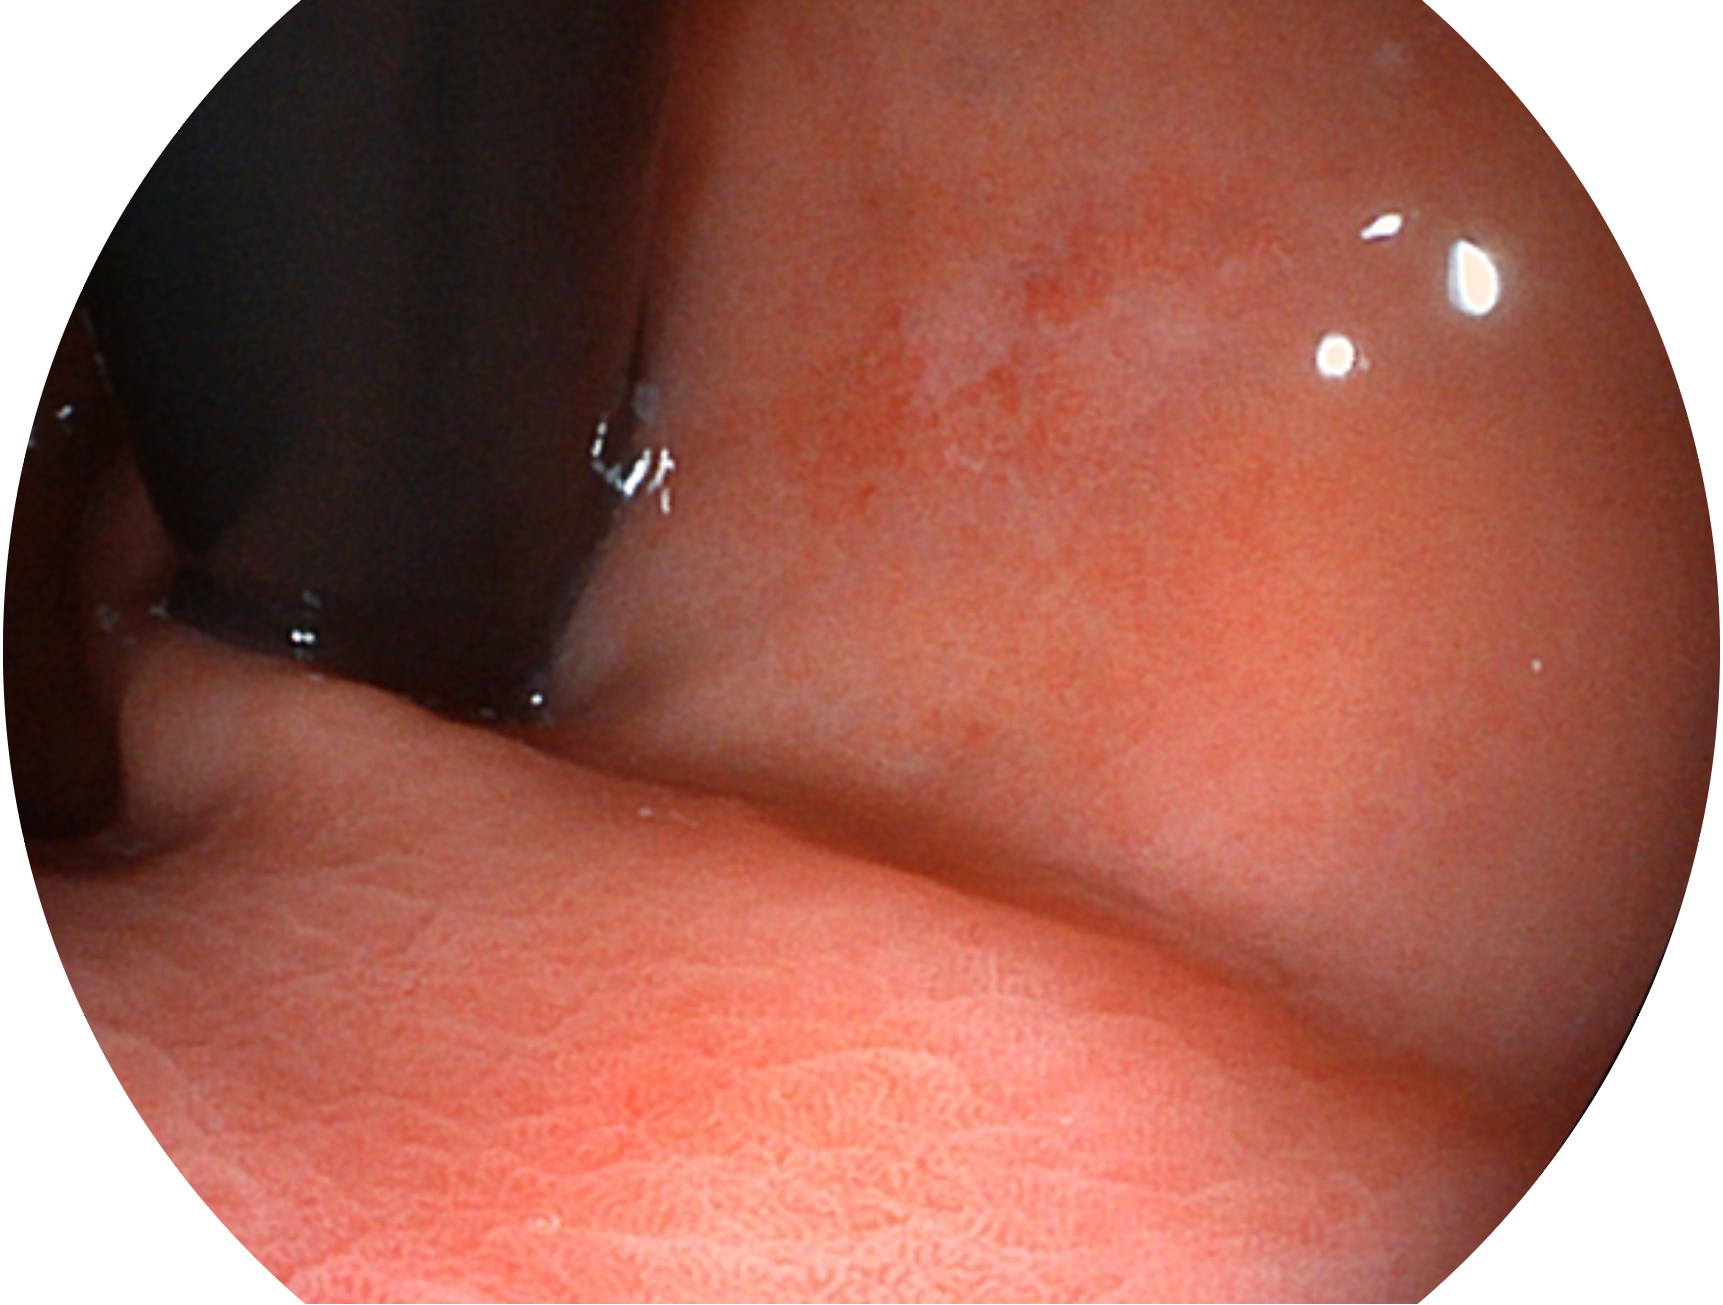

SFI技术是结合特定光谱照明与数字光谱滤波,实现高亮度特殊光成像。染色模式下,不改变粘液、食物残渣、粪液等基本颜色,在保持与白光照明相似的图像色调的同时突显了图像颜色的红白对比度,且在远距离观察的情况下具备与普通白光模式相同的图像亮度,有助于消化道疾病的大范围扫查和早癌筛查。

• 白光图像 SFI图像